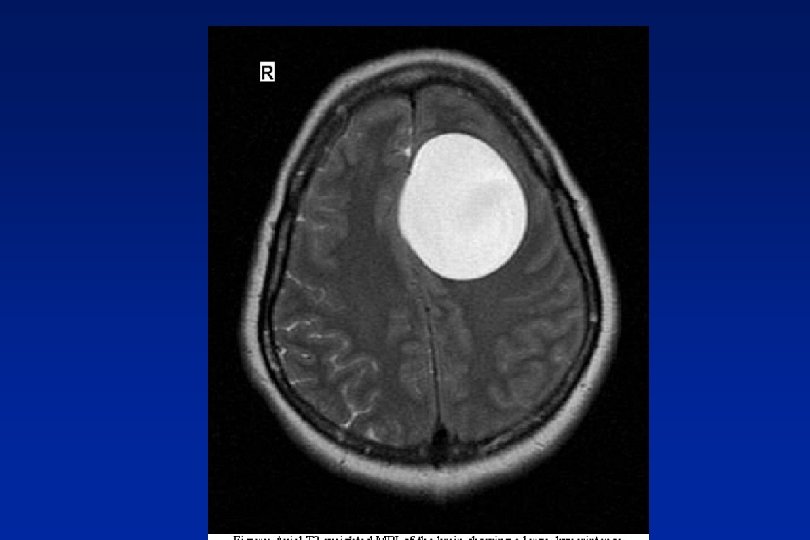

Space occupying lesions Stretch, compression, blockage n Benign – cysts, A-V malformations n Malignant – primary secondary

Red Flags n Abnormal neurological symptoms or signs n History of cancer elsewhere

Orange Flags n Aggregated by Valsalva manoeuvre n Headache with significant change in character n Awakes from sleep n New headache over 50 years n Memory loss n Personality change